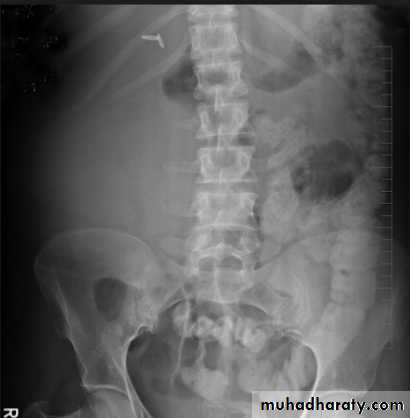

- Over 90% of calculi are radiopaque on plain films and virtually all on CT as very sensitive for detection of calculi, even those that appear radiolucent on plain film.- Most of these stones are a mixture of calcium oxalate and phosphate.

Ddx of stone on KUB :

1. Gall stone2. Calcified LN , cartilage ,fibroid,

3. Phlebolith: round, lucent centre.

Infestation by s.hematobiumCalcification is most important feature, mainly in bladder & lower ureters , but may involve whole ureters .